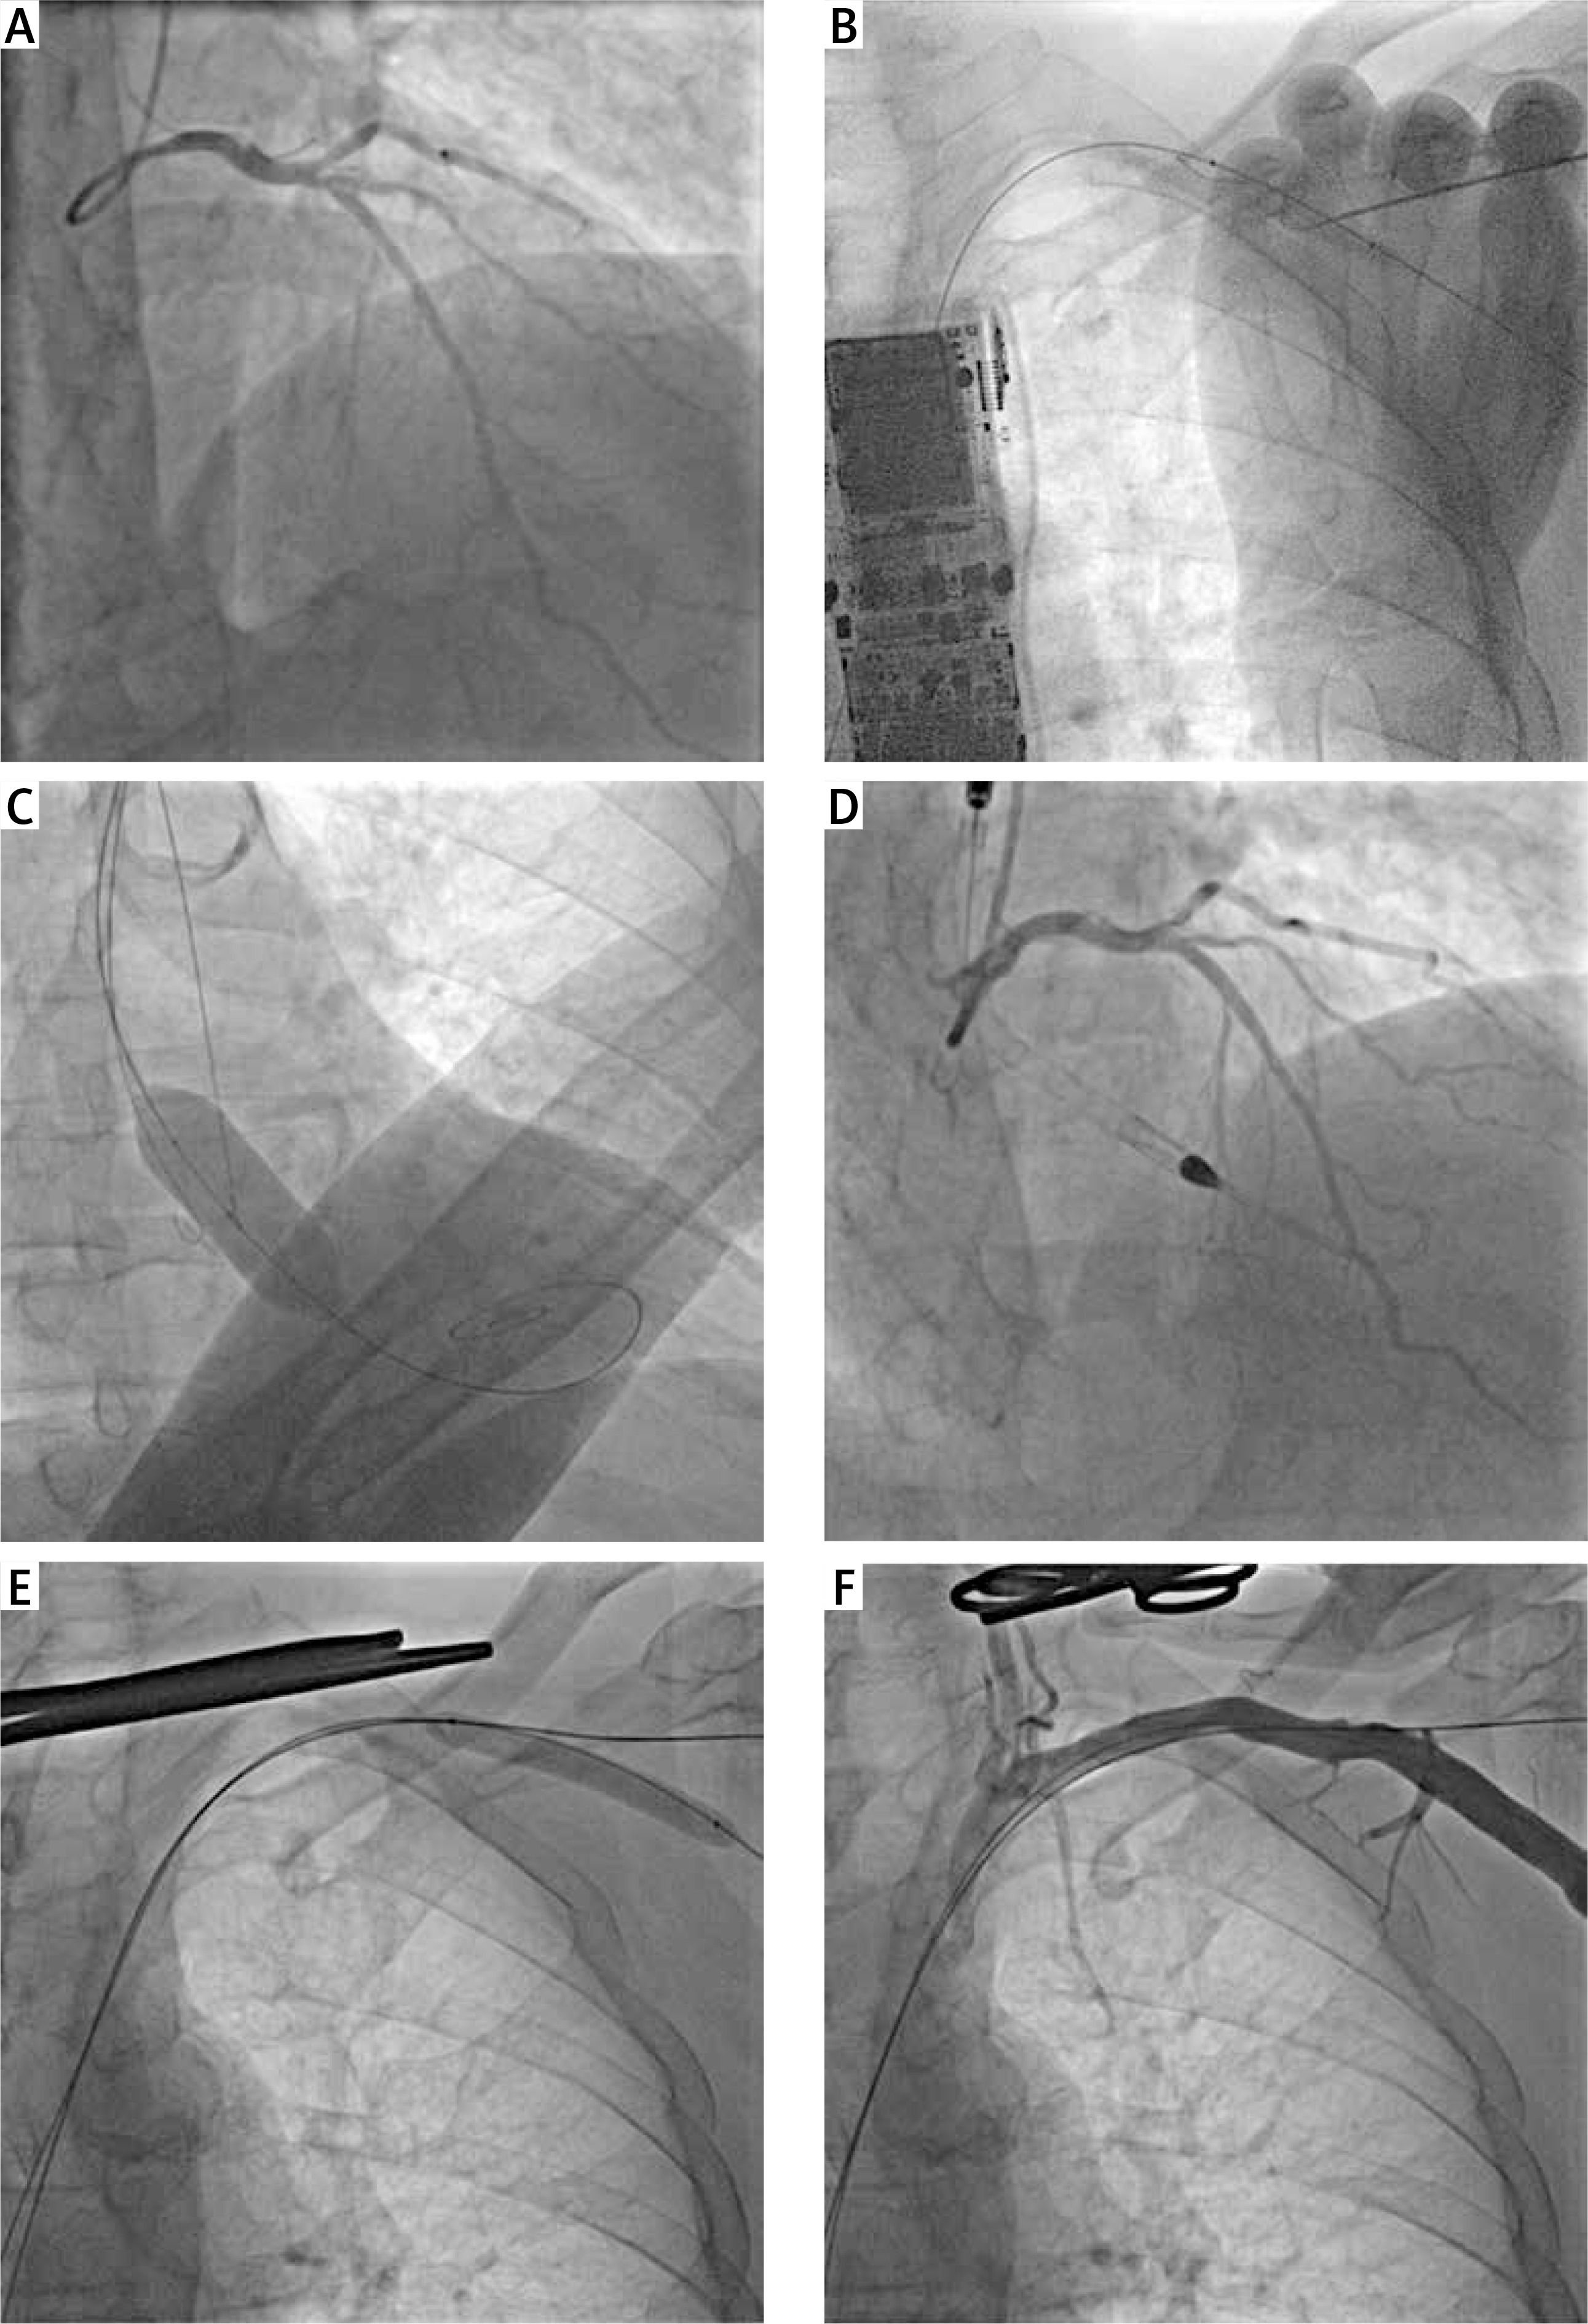

Complex high-risk indicated patients (CHIP) with a limited vascular access constitute a real challenge for percutaneous coronary interventions (PCI), particularly if they require mechanical circulatory support devices. A 73-year-old man with recent non-ST segment elevation myocardial infraction, depressed left ventricular function (ejection fraction, 40%), aortic stenosis (max/mean gradient, 50/32 mm Hg; aortic valve area and its index, 1.0 cm2 and 0.5 cm2/m2) and numerous comorbidities (including recently diagnosed lung cancer in the initial phase) was scheduled by the heart team for balloon aortic valvuloplasty (BAV) and Impella-supported complex PCI of the left main (LM) and the left anterior descending artery (LAD) (Figure 1 A) – the dominant right coronary artery was chronically occluded without the viability of the corresponding myocardium. Due to the abdominal aortic aneurysm with intraluminal thrombus, the procedure could only be performed via upper limb access, and the following interventional images demonstrate how to do it fully percutaneously without general anesthesia.

Figure 1

Interventions via upper limb access. A – Coronary angiography shows the ostial left main and complex left anterior descending artery stenoses – the circumflex artery is rather small. B – The axillary artery was punctured on the fully inflated balloon, then the access-site guidewire was inserted into the balloon, and they were both delivered to the aorta. C – Balloon aortic valvuloplasty was performed (the pre-shaped stiff guidewire was used for rapid pacing). D – The Impella CP was inserted via the left axillary access, but percutaneous coronary intervention was performed via the right radial access with a good final result. E – Balloon tamponade of the access site was employed to prevent torrential bleeding during the removal of the Impella sheath. F – The angiography confirms the successful percutaneous closure of the access site. One can see two guidewires for a possible bailout procedure, i.e.: the access-site guidewire enables an additional placement of Proglides or Angio‑Seal, while the safety guidewire may serve for implantation of stents or covered stents in case of vascular complications

Through the left radial artery, a safety guidewire was inserted into the aorta and the 10/40 mm peripheral balloon was placed within the left axillary artery just below the clavicula, i.e. the access site for the Impella insertion. Under ultrasound imaging and fluoroscopy, the axillary artery and the balloon were punctured (this technique prevents puncturing the opposite arterial wall and the vessel dissection); the access-site guidewire was inserted into the balloon, and then they were both pushed into the aorta (Figure 1 B) [1, 2]. The balloon was replaced with a new one that served as a hemostatic tamponade during maneuvers within the access site. After placing Proglides and the 14F Impella sheath, a pre-shaped stiff guidewire was inserted into the left ventricle, which was used as an electrode for rapid pacing during BAV with a 20/40 mm balloon (Figure 1 C). Then, the Impella CP was implanted via the transaxillary access and PCI of the LM and LAD was performed through the right radial artery (Figure 1 D). After the procedure, the Impella and its sheath were removed during the inflation of the peripheral balloon delivered over the safety guidewire (Figure 1 E) – such a technique prevents bleeding during closing the access site. Finally, the access site was successfully closed percutaneously with Proglides. It should be noted that the safety and access-site guidewires were kept in place until the angiography confirmed a good hemostatic effect (Figure 1 F). In case of vascular complications, the safety guidewire may serve for implantation of stents or covered stents, but the access-site guidewire may be used for additional Proglides or Angio-Seal delivery – such a technique makes the axillary approach quite safe [1–3]. Several days later the patient was discharged home in a good condition.